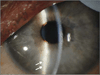

Among the survivors of Ebola virus disease (EVD), complications that include uveitis can develop during convalescence, although the incidence and pathogenesis of EVD-associated uveitis are unknown. We describe a patient who recovered from EVD and was subsequently found to have severe unilateral uveitis during convalescence. Viable Zaire ebolavirus (EBOV) was detected in aqueous humor 14 weeks after the onset of EVD and 9 weeks after the clearance of viremia.